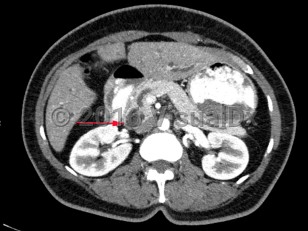

Carcinoma of the ampulla of Vater encompasses tumors that arise from within the ampullary complex (duodenal aspect of sphincter of Oddi, distal common bile duct [CBD], distal pancreatic duct, and papilla of Vater). These tumors often arise as part of a genetic syndrome, most commonly familial adenomatous polyposis (FAP) or hereditary nonpolyposis colorectal cancer (HNPCC), which tends to occur in a younger population. Patients with FAP require screening for duodenal adenomas including ampullary adenomas at the onset of colonic polyps or around age 25. Sporadic ampullary carcinomas typically occur around age 60-70.

Histologically, ampullary carcinomas can be divided into intestinal or pancreaticobiliary in origin. The intestinal type is more prevalent and is linked to mutations in KRAS and COX-2. Patients with intestinal-type ampullary carcinoma have a better prognosis. Painless jaundice (Courvoisier sign) is the most common clinical manifestation of ampullary carcinoma. This is caused by mechanical compression of the distal CBD by tumor. The remainder of patients can present with iron deficiency anemia or occult gastrointestinal tract bleeding. Silver stool may occur. More vague symptoms such as abdominal pain, nausea, fever, and dyspepsia can also occur.